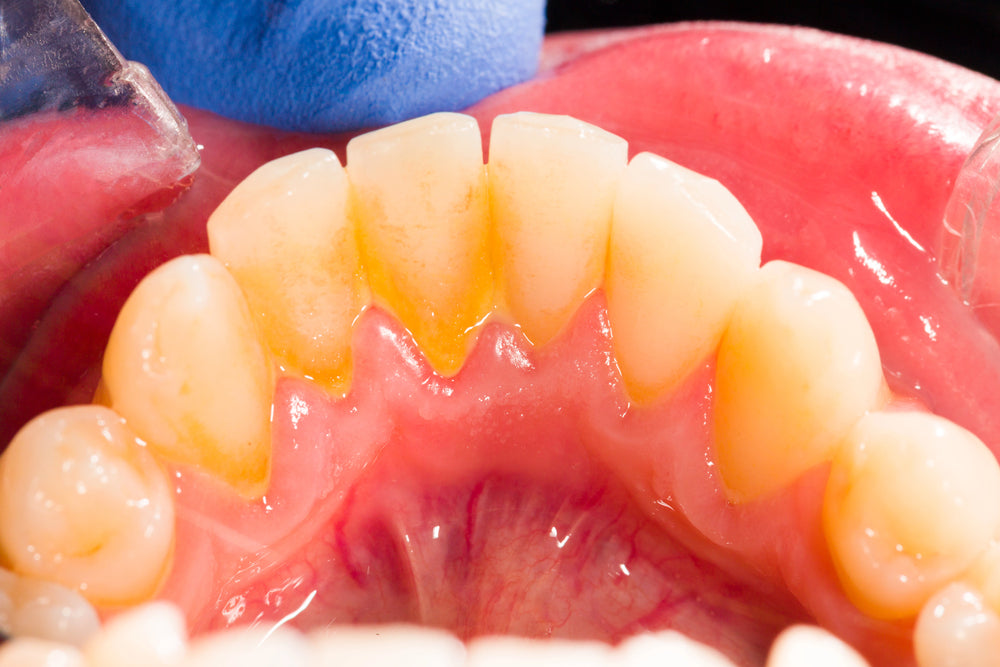

Dental plaque is a sticky and colorless or light yellow film that's constantly forming over the teeth. The bacteria could cling to Plaque and produce acids which may cause tooth decay.

The formation of plaque begins on the teeth after 4-12 hours of brushing . That’s why it's crucial to practice a good oral hygiene routine and regular dental hygiene that can assist in removing and avoiding plaque. The plaque, which is made up of bacteria, develops between your teeth as well as on the line of your gums.

What causes plaque on teeth? It's bacteria. Certain bacteria can be beneficial, but some can accumulate on your teeth's surfaces and form a plaque biofilm. It's usually located near your gum line. Although it's common and normal, it is important to keep the sugar from mixing with it. The bacteria feed off sugars and produce acids that can cause plaque on teeth.

Plaque is a sticky film that continually forms on teeth and gums, typically consisting of bacteria, food debris, and saliva. Plaque can lead to tooth decay, gum disease, and bad breath when left unremoved on a regular basis. Plaque can be removed easily by brushing your teeth regularly.

Tartar (Calculus): Tartar is a harder form of plaque that occurs when plaque isn't adequately removed from teeth.

• Tooth Discoloration - Plaque has a yellowish tint and can stain teeth over time, leading to noticeable yellow or brown discolorations of your smile.